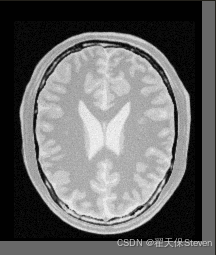

过程图像如下:

固定图像

浮动图像